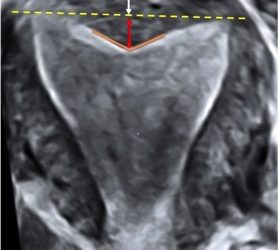

Anche a Ottobre un nuovo video "How to do"! Questo mese scopriremo come definire ecograficamente le anomalie congenite del tratto...